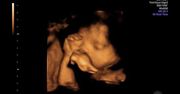

Dominika Gwit przyznaje, że w życiu prywatnym nie jest aż taką kokietką, jak grane przez nią bohaterki, ale też potrafi zawalczyć o swoje. Na swój sposób uwodzi męża, ale zapewnia, że nie jest to wyrafinowana gra. Jako żona czuje się szczęśliwa i spełniona. Wierzy też, że przyjdzie odpowiedni moment na dziecko. Dominika niedawno przyznała, że "każda kobieta, kiedy wyjdzie za mąż, myśli o tym, żeby urodzić dziecko". Celebrytka, mimo publicznych przygotowań do macierzyństwa, zapewnia, że nie czuje presji ze strony najbliższych ani partnera. Jako szczęśliwa mężatka spełnia się zawodowo i życzy sobie, żeby kolejny rok również obfitował w dobre wydarzenia.